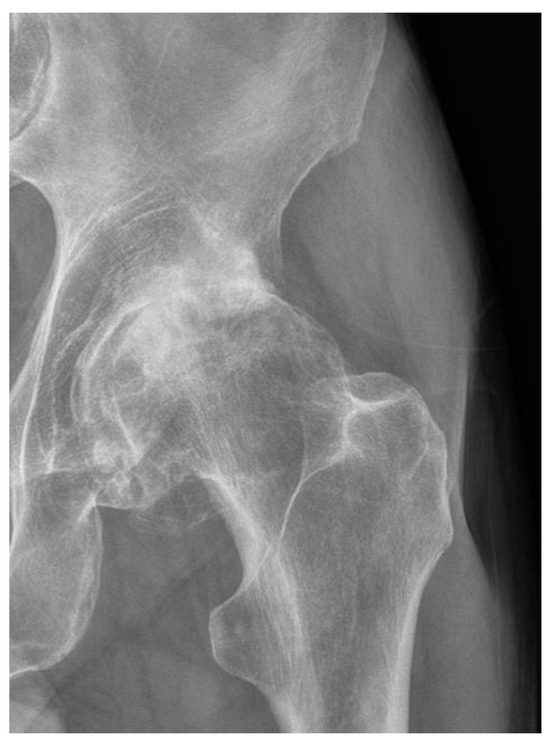

- Kellgren, J.H.; Lawrence, J.S. Radiological Assessment of Osteo-Arthrosis. Ann. Rheum. Dis. 1957, 16, 494–502. [Google Scholar] [CrossRef]

- Mark, D.; Kohn, B.A.; Adam, A.; Sassoon, M.D.; Navin, D. Classifications in Brief: Kellgren-Lawrence Classification of Osteoarthritis. Clin. Orthop. Relat. Res. 2016, 474, 1886–1893. [Google Scholar] [CrossRef]

| Grade | Radiological Findings |

|---|---|

| 0 | Normal |

| 1 | Doubtful narrowing of joint space and possible osteophytic lipping |

| 2 | Definite osteophytes, definite narrowing of joint space |

| 3 | Moderate multiple osteophytes, definite narrowing of joint space, some sclerosis, and possible deformity of the bone contour |

| 4 | Large osteophytes, marked narrowing of joint space, severe sclerosis, and a definite deformity of bone contour |